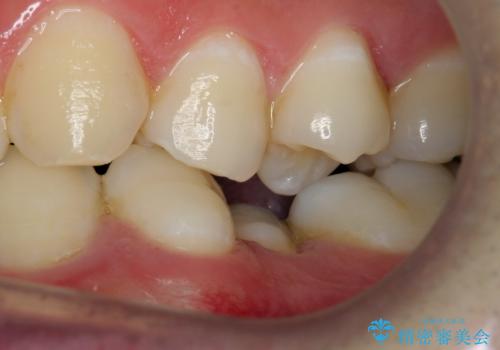

①上下左右合計4本抜歯(口元は一番下がるプラン、上の奥歯をさらに後ろに下げる必要があるため②より時間がかかる、上下正中は合う)

②上の歯を2本抜歯、下の歯は前歯1本と最小限の抜歯(矯正治療は早く終わる、口元は下がる、抜歯は3本、上下の正中は合わない)

を提示し、

②を選択されました。

下顎がとても小さく後方位であるため、オトガイの閉口時のシワは完全になくすことは難しかったですが、前歯も大きく下がり満足していただきました。